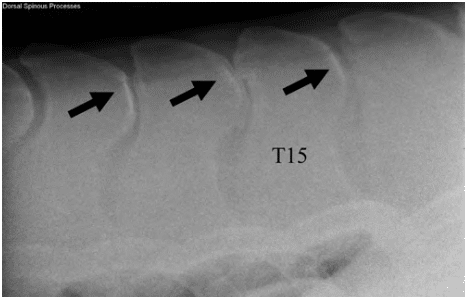

Radiograph showing typical kissing spines (black arrows)

Photo courtesy Dr. Tracy Turner

Kissing spines typically occurs in the thoracic spine, where the saddle would sit. Veterinarians most commonly find the condition from the 13th to the 18th thoracic vertebrae but have seen it as far cranial (forward) as the 11th thoracic vertebra. Occasionally kissing spines can be detected in the lumbar spine. There appears to be a hereditary component to kissing spines, but scientists have not confirmed any genetic factors beyond changes to specific regions on Chromosomes 16 and 25. Also, horses’ height seems to have a strong impact on their likelihood to have kissing spines, while sex and age seem to have less significant roles. Environmental and management factors such as saddle fit, the way the horse travels under saddle and the quality of the riding and training the horse receives could play a role, but researchers have not established definitive correlations.

Veterinarians can readily diagnose kissing spines using radiographs (X rays) of the back. Physiologic imaging techniques such as thermography and nuclear scintigraphy (bone scans) can help determine if inflammation or active bony remodeling accompanies the radiographic changes. To assess whether kissing spines are clinically relevant or cause for concern, practitioners should combine imaging results with a clinical exam and the horse’s history.